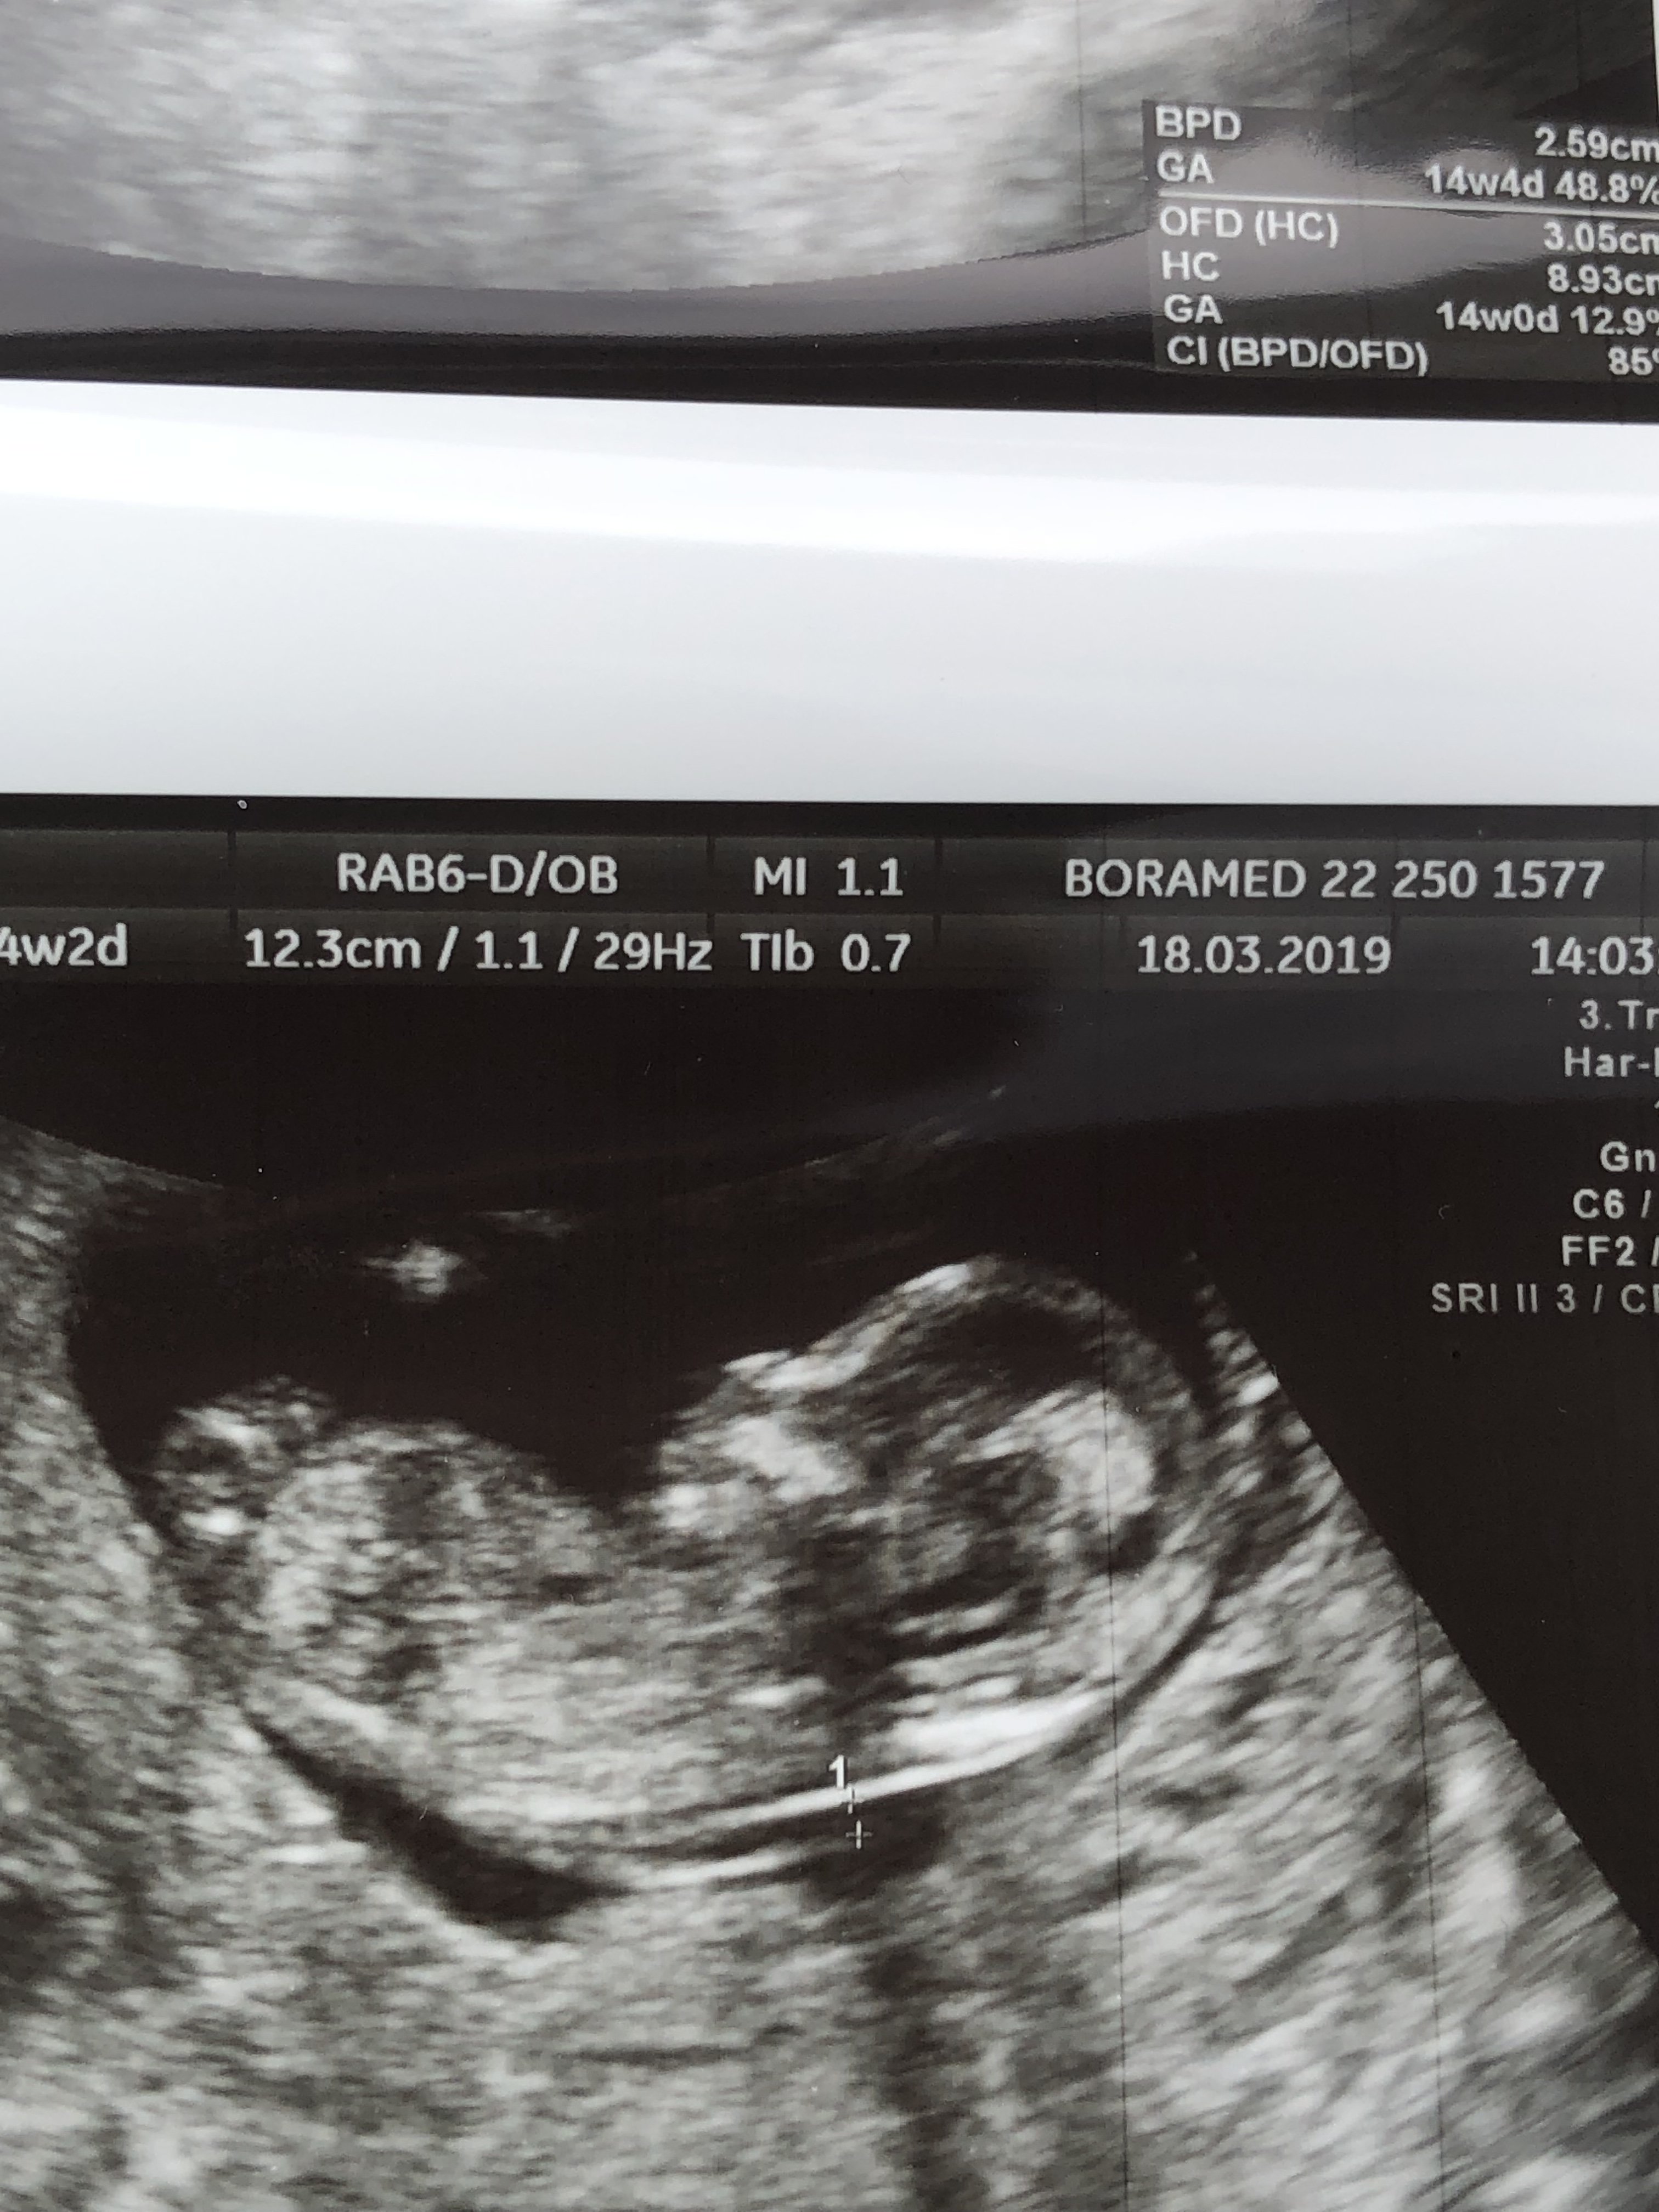

Cześć :) to może i Ja skorzystam z waszej uprzejmości ;) na 90% lekarz stwierdził, że chłopiec :) ale powiem szczerze, że dla mnie to zdjęcie to czarna magia ;) ja się nadal zastanawiam czy to nie jest pępowina ;) oczywiście dla mnie to obojętne co będzie, ale nie ukrywam, że ciekawość jest silniejsza :)

IMG_20190222_081650251.jpeg